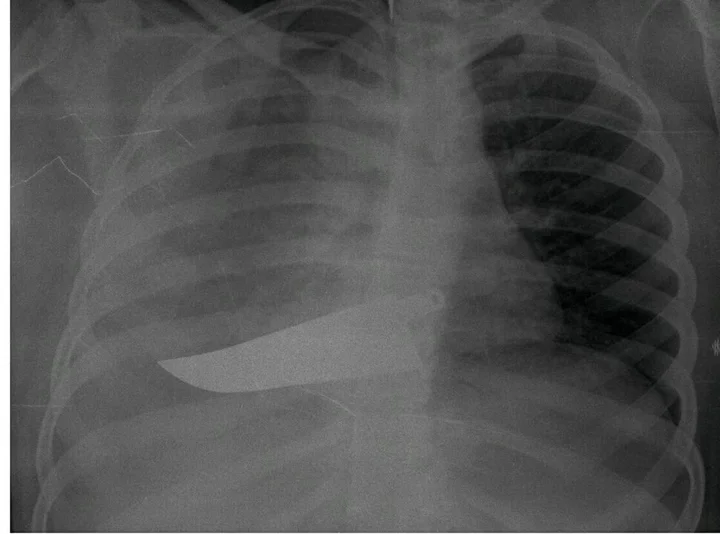

This isn’t the beginning of a novel, but the true story of a woman featured in “Invisibility Is Not A Superpower,” an exhibition that was set up in the atrium of the San Carlo Hospital in Milan, Italy, from Nov. 21 to Dec. 8. Through anonymous photographs and X-rays, the exhibition recounts the tragedy of women arriving at the emergency room and reporting that they have been victims of domestic violence.

“In this exhibition, a voice is given to the bodies and injuries of women who have suffered violence, weaving individual stories into a single narrative,” said photographer Marzia Bianchi. “The lives of the women differ, yet the pattern of violence is repeated, mainly at the hands of a partner, relative or acquaintance.”